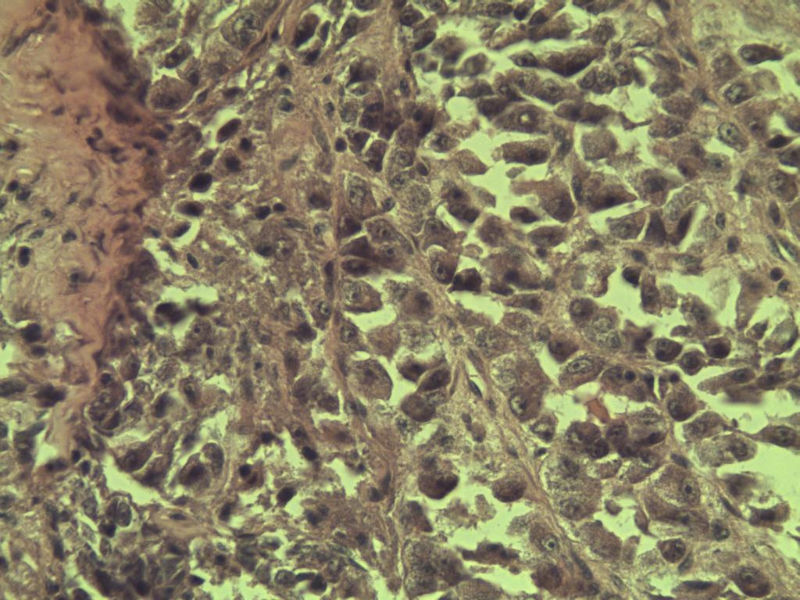

女 70岁 右颈部 头皮 多发皮下结节      取颈部部分结节送检 灰白小组织 1 块,直径 0.4 cm。 请问这个是什么?

肿瘤细胞大,上皮样,核空泡状,核仁明显,胞质嗜酸性或透明。

考虑:恶性黑色素瘤?

近心型上皮样肉瘤?

软组织透明细胞肉瘤?

上皮样多形性脂肪肉瘤?

等免疫组化标记!

此片染色欠佳,取材或切面也有问题,加大了诊断的难度,恶黑确实需要考虑,但其他一些转移癌也需要排除,比如肺癌之类的,还是期待免疫组化!